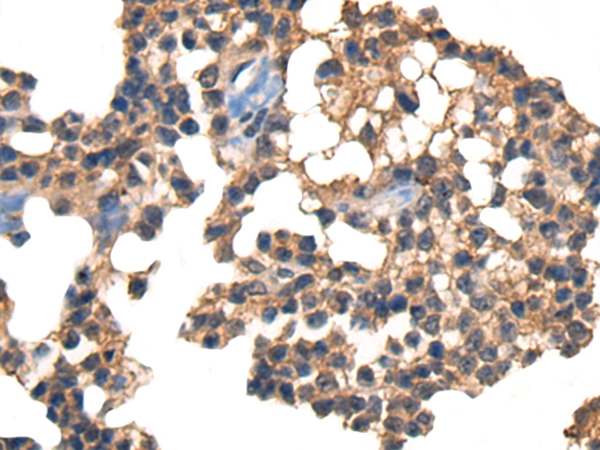

The image on the left is immunohistochemistry of paraffin-embedded Human ovarian cancer tissue using 46450(CDH17 Antibody) at dilution 1/35, on the right is treated with synthetic peptide. (Original magnification: x200)